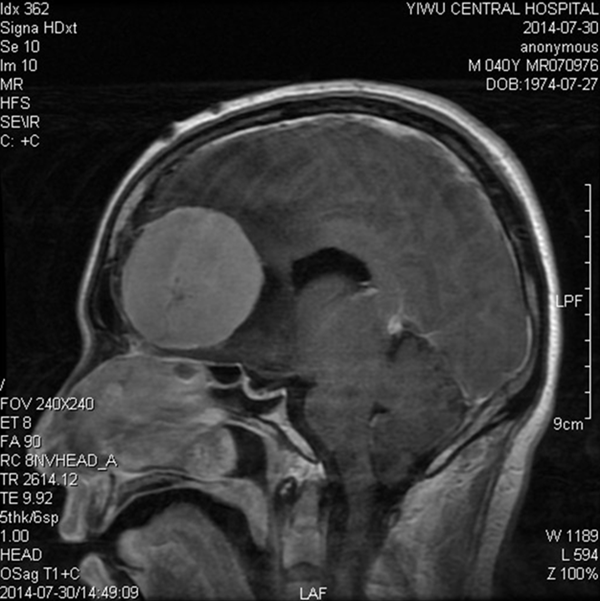

今年7月,小金经不起妻子的多次催促,到浦江某医院就诊,CT检查结果,把接诊的医师吓了一跳:小金的颅内居然长了一个巨大的肿瘤,占据了前颅窝的大部分位置。恐惧和忧伤击跨了小夫妻俩。一家人吃不下饭,睡不着觉。经人介绍,慕名前来我院就医。7月27日,金某入住神经外科病区后,经头颅CT检查,发现他的左额溴沟处有一个鹅蛋大小的巨大肿瘤,几乎占了整个大脑的1/6。

据神经外科主任医师陶志强介绍,溴沟脑膜瘤是颅底脑膜瘤的一种,由于病变位置较特殊,手术操作空间小,供血来源复杂,且与双侧大脑前动脉,以至脑垂体柄结构相邻,术中稍有不慎,可能会出现难以控制的大出血,后果不堪设想。尽管风险极高,但考虑到手术是挽救病人生命的唯一手段,还是大胆决定进行手术治疗,并制订了严密的手术方案,准备了二套电凝止血和吸引设备。